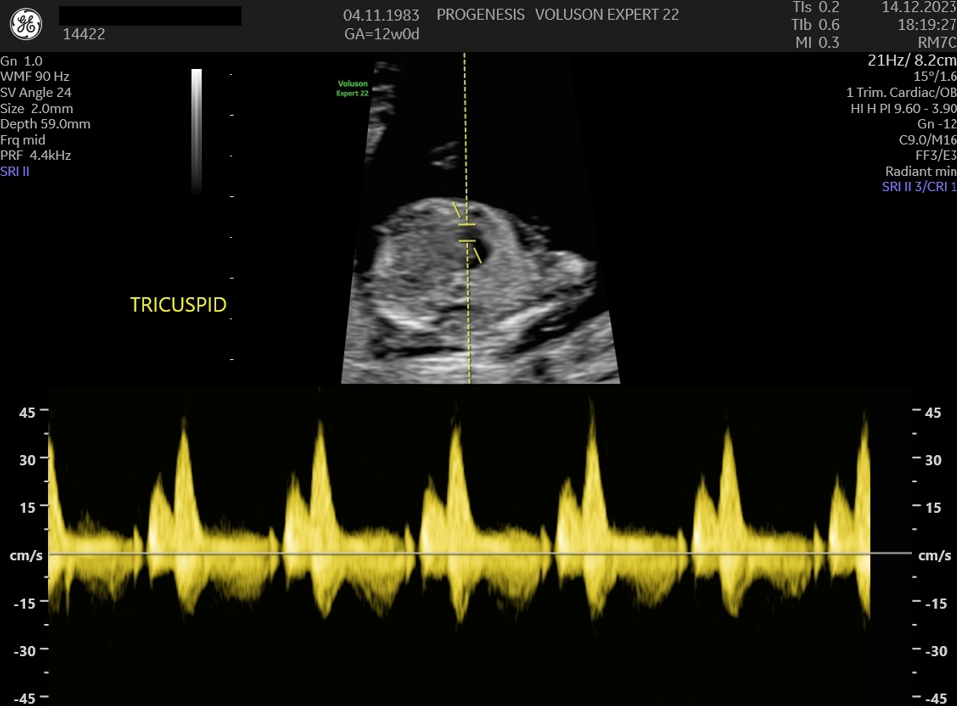

Εξαρτάται από την ηλικία της, το ιστορικό των προηγούμενων κυήσεων, την αξιολόγηση στο έμβρυο υπερηχογραφικών δεικτών όπως, της αυχενικής διαφάνειας, του ρινικού οστού, της ροής στην τριγλώχινα βαλβίδα και το φλεβώδη πόρο, ανατομικές ανωμαλίες που πιθανά να συνδέονται με χρωμοσωμικά/ γενετικά σύνδρομα καθώς και τη μέτρηση τριών ορμονών (PAPP-A, free βHCG και PLGF) στο αίμα της μητέρας.

Πολλές και σημαντικές ανωμαλίες, όπως ανεγκεφαλία, απουσία άκρων, ομφαλοκήλη, ορισμένες συγγενείς καρδιοπάθειες και άλλες ανωμαλίες, είναι ορατές απ' αυτό το στάδιο της κύησης. Δίνουμε ιδιαίτερη έμφαση στην αξιολόγηση της καρδιάς των εμβρύων, τόσο για την αξιολόγηση χρωμοσωμικών ανωμαλιών όσο και πρώιμη ανίχνευση συγγενών καρδιοπαθειών από το 1ο κιόλας τρίμηνο (π.χ. υποπλασία καρδιάς, συγγενή μετάθεση μεγάλων αγγείων).